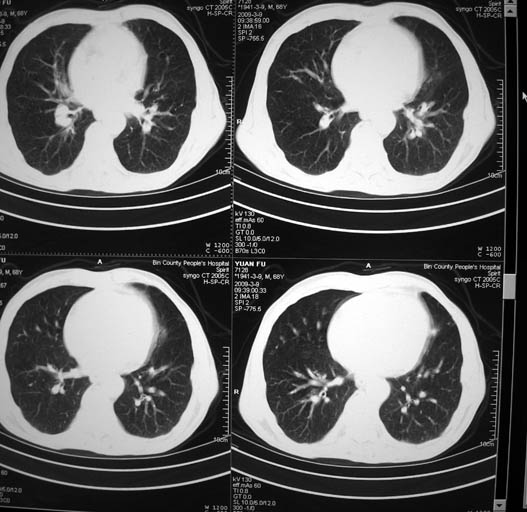

标题: CT18577:男,68岁,左肺占位。 [打印本页]

标题: CT18577:男,68岁,左肺占位。

男,68岁,左上肺占位,肺门淋巴结转移?

1)考虑左肺上叶尖段周围型肺癌并阻塞性肺炎,纵隔淋巴结转移。2)心包少量积液。

考虑左肺上叶尖段周围型肺癌并阻塞性肺炎,纵隔淋巴结转移.

1)考虑左肺上叶尖段周围型肺癌并阻塞性肺炎,纵隔淋巴结转移。2)心包少量积液

1)考虑左肺上叶尖段周围型肺癌并阻塞性肺炎,纵隔淋巴结转移。

2)心包少量积液。

考虑两肺播散性肺结核